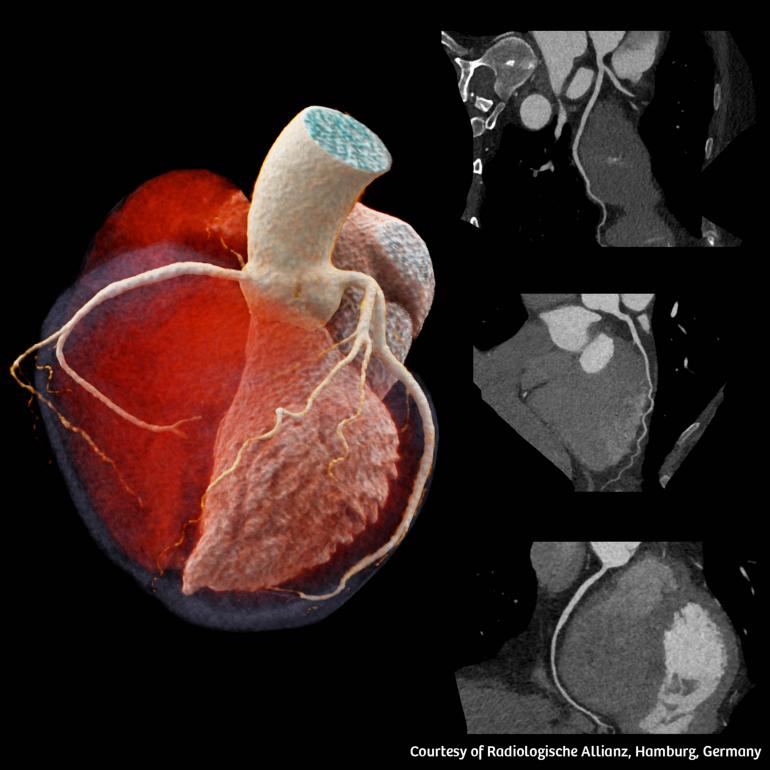

Η αξονική τομογραφία διπλής λυχνίας επιτρέπει την ιδιαίτερα υψηλή χρονική ανάλυση. Η υψηλή χρονική ανάλυση και η ταχύτητα σάρωσης αποτελούν σημαντικά στοιχεία στην αξονική τομογραφία καρδιάς, διότι περιορίζουν τα παράσιτα στην εικόνα λόγω της αναπνευστικής κίνησης ή της κίνησης της καρδιάς. Αυτό επιτρέπει τη σάρωση ασθενών με απαιτητικές κλινικές καταστάσεις, όπως ασθενείς που έχουν υψηλούς ή ακανόνιστους καρδιακούς παλμούς, αδυνατούν να συγκρατήσουν την αναπνοή τους ή αδυνατούν να μείνουν ακίνητοι, αλλά και ασθενείς που δυσκολεύονται να ακολουθήσουν τις οδηγίες του κλινικού ιατρού. Η χρήση φίλτρου κασσίτερου διατηρεί τη δόση ακτινοβολίας σε χαμηλά επίπεδα, διατηρώντας παράλληλα τη βέλτιστη ποιότητα εικόνας, ιδίως σε κλινικές ενδείξεις, όπως προληπτικού ελέγχου σαρώσεις θώρακα με εξαιρετικά χαμηλή δόση.

Στις δυνατότητες του SOMATOM Pro.Pulse αναφέρθηκε και ο Δρ. Quoc-Duy Vo, Διευθυντής του ακτινολογικού τμήματος στο Νοσοκομείο Morges στην Ελβετία2 και τόνισε: «Χαιρόμαστε που θα μπορέσουμε επιτέλους να χρησιμοποιήσουμε αυτή την υψηλή τεχνολογία στη μονάδα μας. Ο κλινικός ρόλος της αξονικής τομογραφίας επεκτείνεται, καθώς αναδεικνύεται σε βασικό παράγοντα για την έγκαιρη ανίχνευση και τον σχεδιασμό της θεραπείας. Γι’ αυτό το λόγο, χρειαζόμαστε ένα υψηλής απόδοσης σύστημα που να επιτρέπει τη διενέργεια εξετάσεων σε μία ακόμη πιο διευρυμένη ομάδα ασθενών. Με το SOMATOM Pro.Pulse μπορούμε να εκτελούμε υψηλής ποιότητας καρδιολογικές απεικονίσεις, καθώς και ιατρικές απεικονίσεις σε άλλους τομείς της ακτινολογίας».